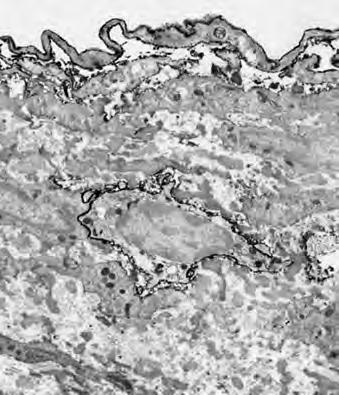

Sąsiednia strona pokazuje zdjęcie komórki rakowej pod mikroskopem elektronowym, powiększonej 6.500 razy. Ten typ komórki nazywamy rakiem (od greckiego “carcinoma”), co oznacza, że wywodzi się ona z komórek nabłonkowych, które wyściełają zarówno wewnętrzną (tzn. płuca, jelita) i zewnętrzną (skóra) powierzchnię ciała.

W tak znacznym powiększeniu możemy zidentyfikować niektóre z charakterystycznych cech wszystkich komórek rakowych: a) wielkie, nietypowego kształtu jądro komórkowe, odzwierciedlające wysoką zdolność reprodukcyjną komórek rakowych oraz b) nierówną, złożoną błonę komórkową, odzwierciedlającą wysoką aktywność wydzielniczą substancji produkowanych w komórkach rakowych.

Jedną z najważniejszych cząsteczek wydzielanych w wielkich ilościach przez komórki rakowe są enzymy trawiące kolagen („nożyce”). Na ilustracji są one przedstawione w formie czerwonych kulek z otwarciem, przypominających postaci z popularnej gry komputerowej Pac-Man.